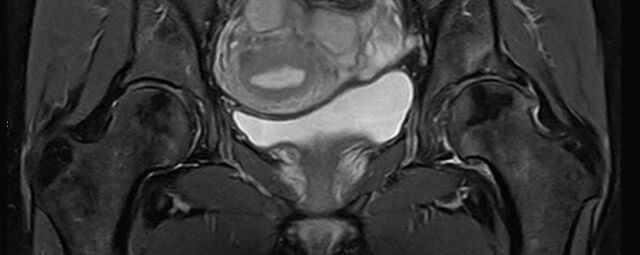

• Urogenitalorgane

• Tumordiagnostik z.B. im Bereich der Ovarien, des Uterus, der Prostata oder Harnblase

• dynamische MR-Analyse bei Beckenbodeninsuffizienz